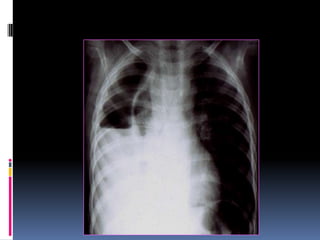

Over penetrated Film

 Lung fields darker than

normal—may obscure subtle

pathologies

•   See spine well beyond the

diaphragms

•   Inadequate lung detail

Over penetrated Film Lung fields darker than normal—may obscure subtle pathologies • See spine well beyond the diaphragms • Inadequate lung detail